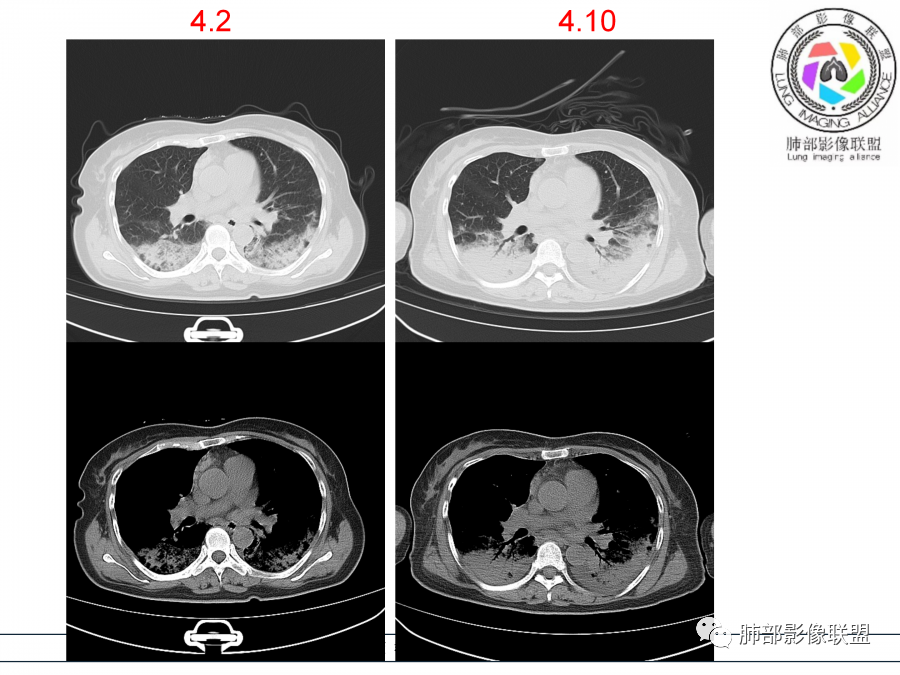

影像,第一次双肺中下叶胸膜下多发斑片状实变影,部分融合成,周围散发磨玻璃影,磨玻璃影内可见小叶间隔及小叶内间隔增厚,病变平行于胸膜,第二次间隔8天,双肺实变影明显进展,有重力作用,支气管近端堵塞,进展较快,临床有发热,血沉高,狼疮SLE阳性,考虑1:OP(机化性肺炎)2:SLE相关肺炎,建议支气管镜灌洗液病原学检测。

第一次双肺中下叶胸膜下多发斑片状磨玻璃及实变影,病变平行于胸膜,支气管通畅,8天后,双肺实变影明显进展范围扩大,部分支气管近端堵塞,进展较快,胸腔积液,抗感染治疗无效,考虑:非感染性疾病:结缔组织相关性肺病。鉴别机化性肺炎。